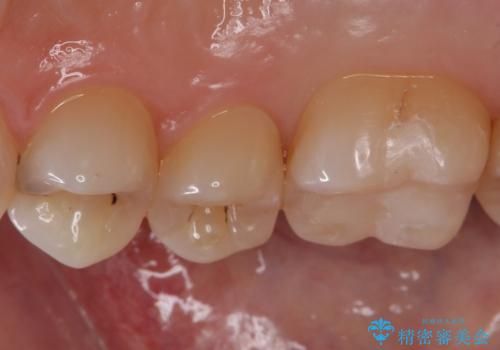

銀歯をセラミックにやり替えることで審美性を改善することができます。

適合の良いセラミックインレーを装着することで、今後の虫歯発生リスクを抑えることができます。